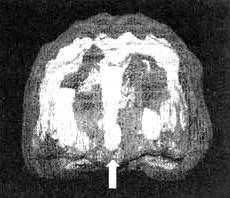

Мозг Гейл. Обсессивно-компульсивное расстройство (ОКР)

Трехмерное изображение — активный мозг, вид спереди. Обратите внимание на значительное усиление активности в поясной системе (см. стрелку).